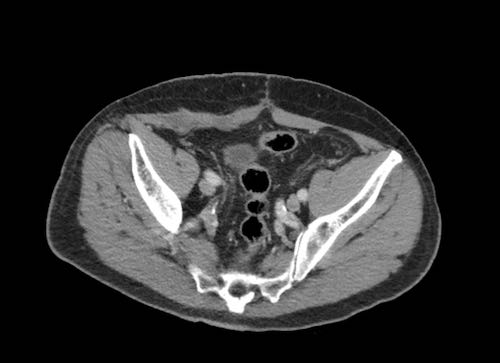

Ca lâm sàng 2

Cuộn qua các lát cắt.

Bạn có thể phát hiện tất cả các tổn thương cấy ghép phúc mạc không?

.jpeg)